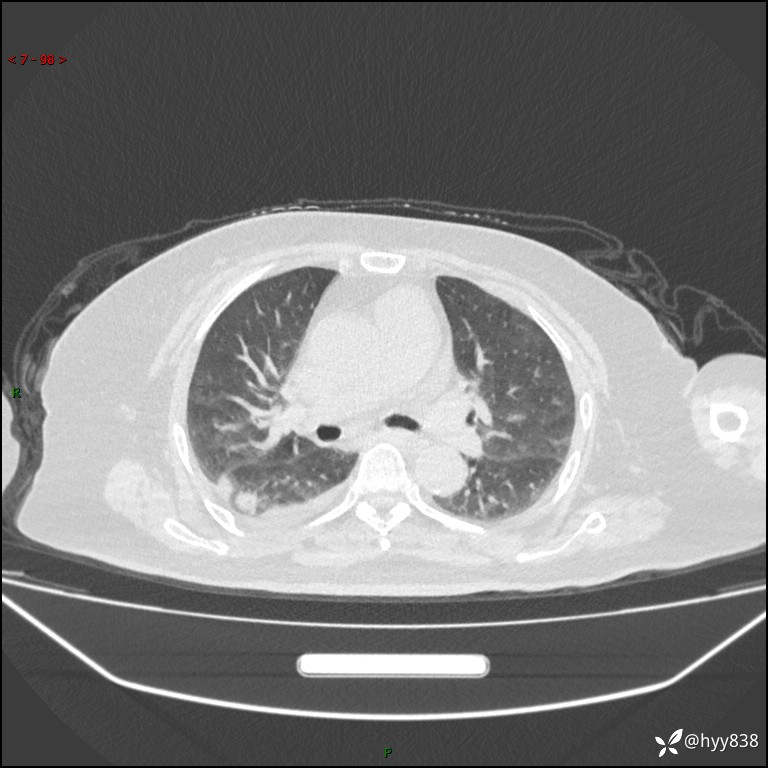

患者性别:女

患者年龄:57岁

简要病史:昏迷入院

临床诊断:昏迷

胸部 CT平扫、